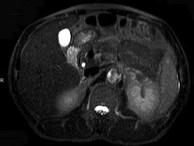

问题 男,52岁,下肢无力伴多饮多尿2年余,实验室检查:低血钾,血醛固酮水平及24小时尿醛固酮定量超过正常值,MRI检查如图所示,应诊断为()

选项 A.左肾上腺囊肿 B.左肾上腺腺瘤 C.左肾上腺嗜铬细胞瘤 D.左肾上腺髓脂瘤 E.左肾上腺转移瘤

答案 B